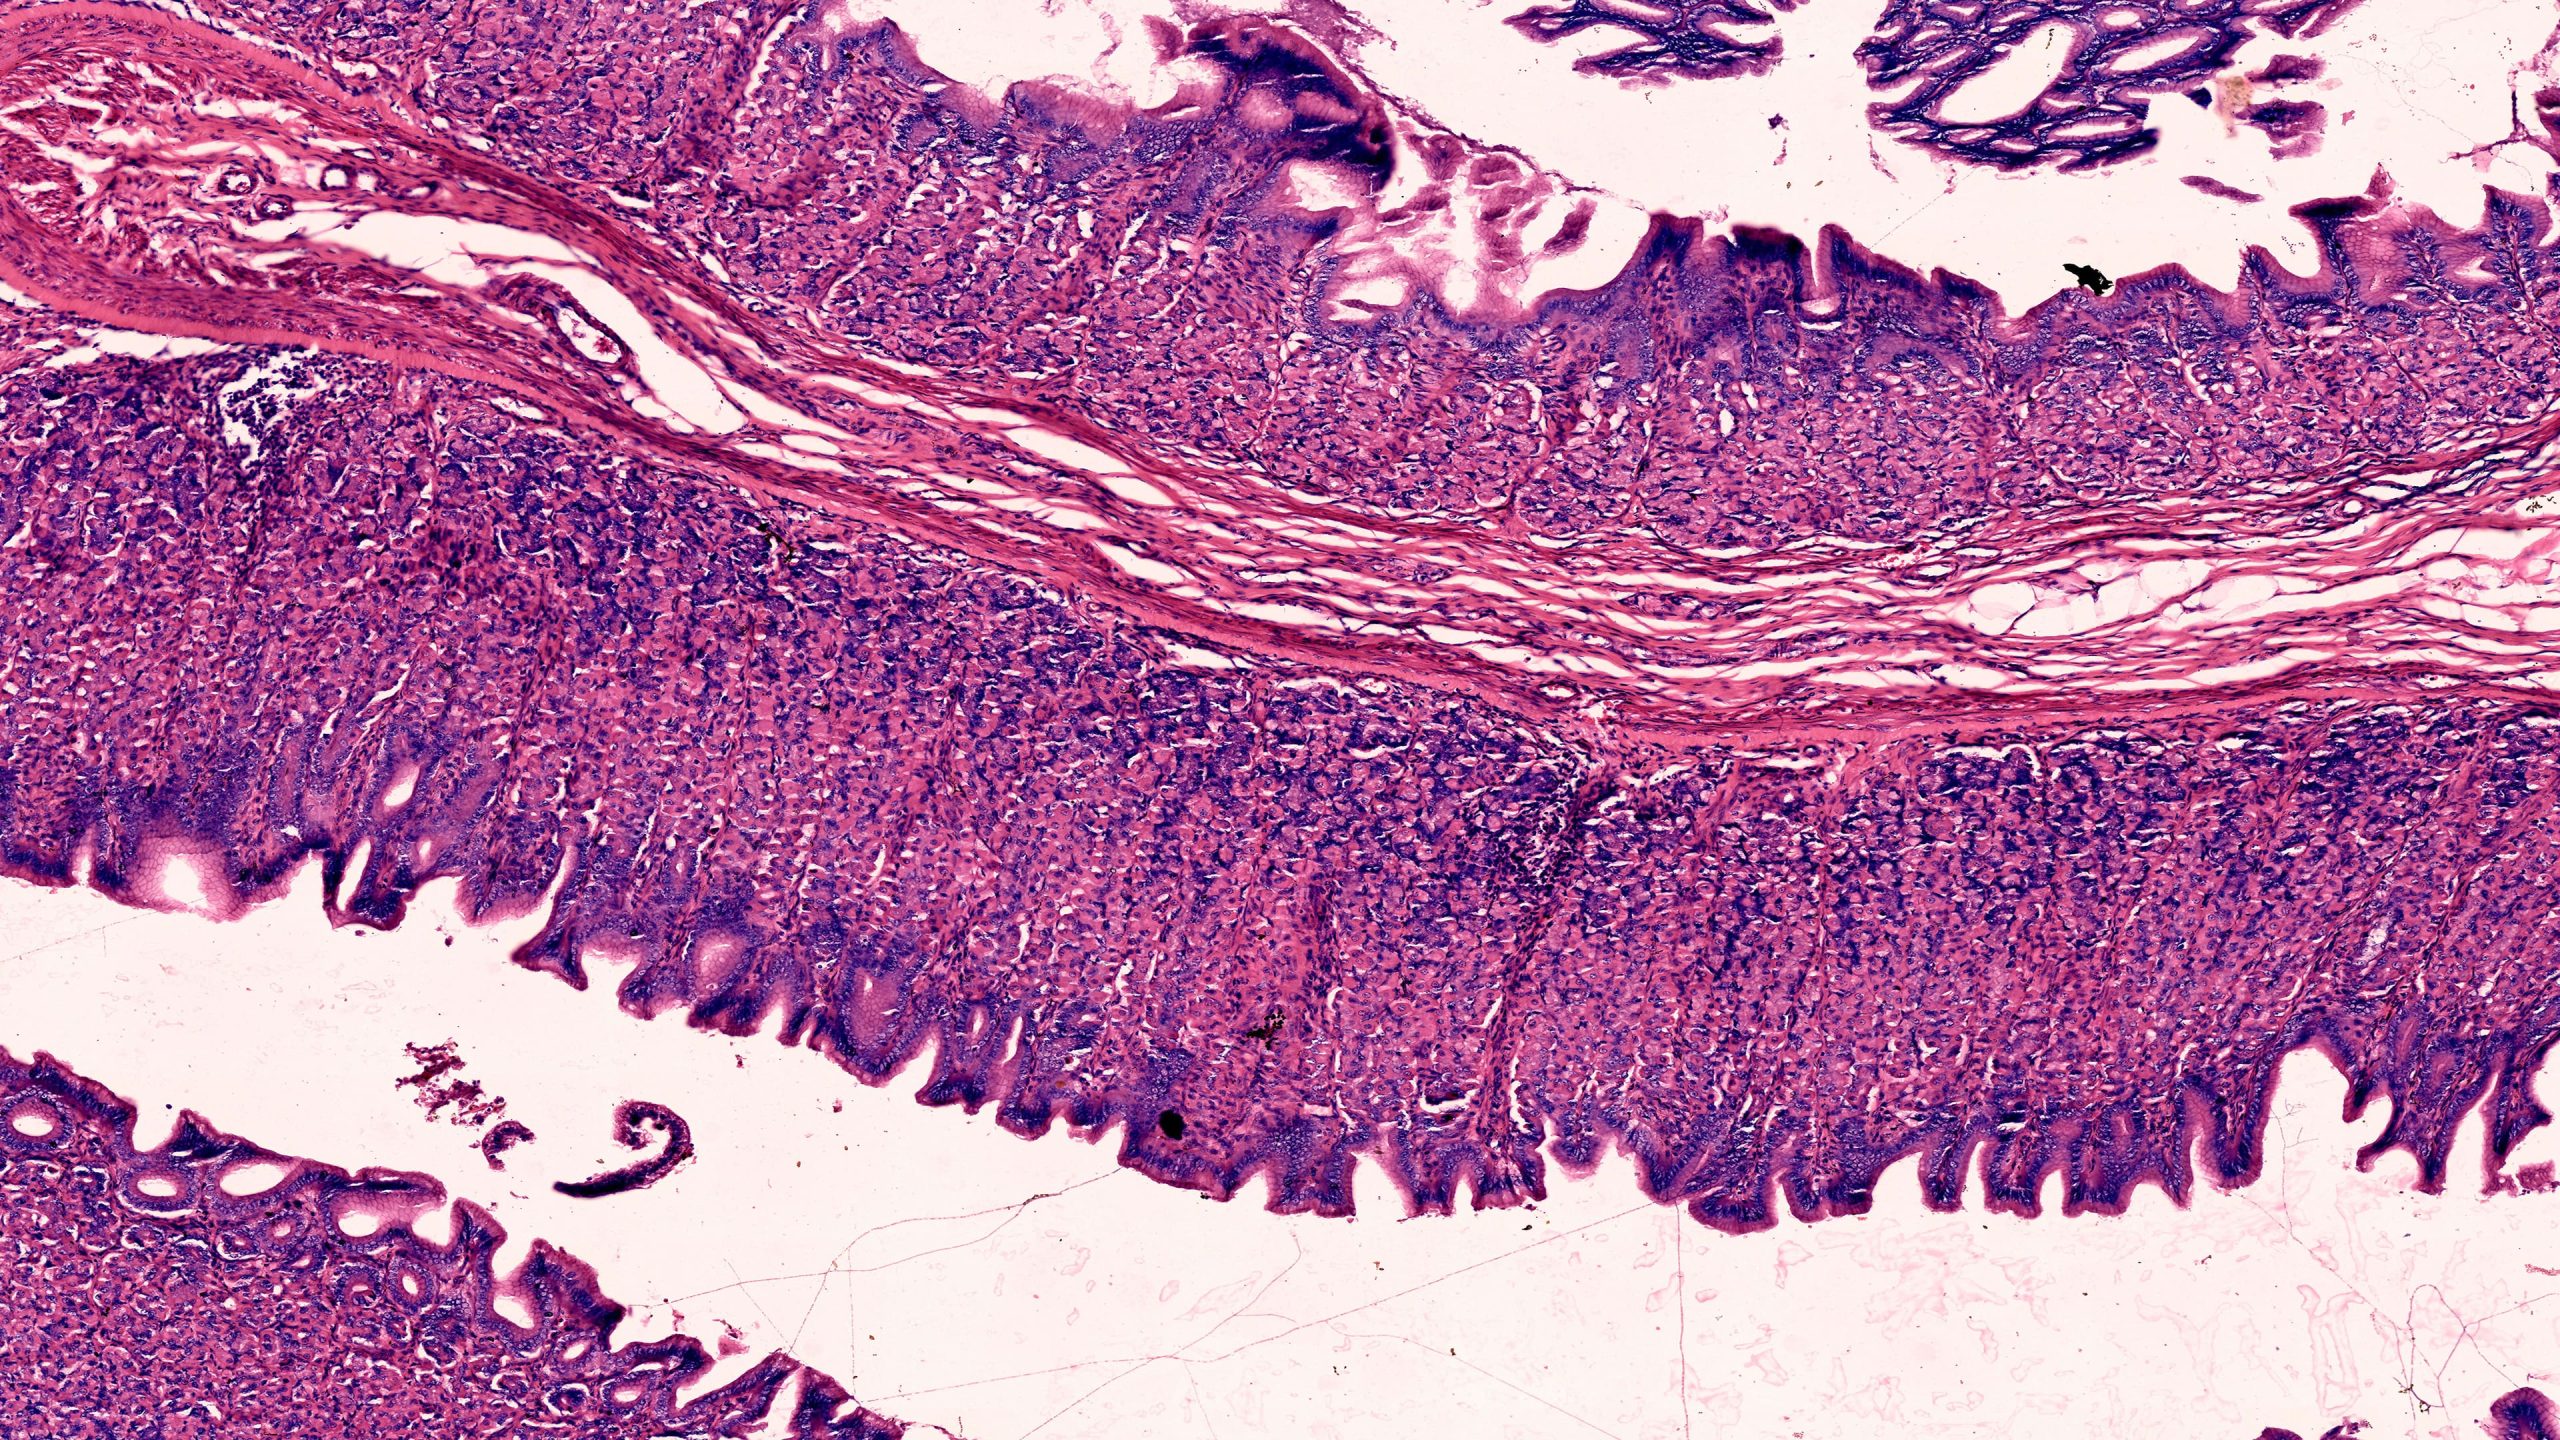

Stomach Pylorus 40X